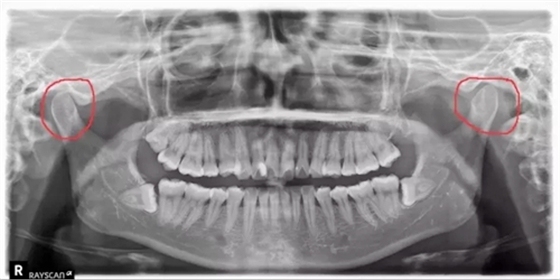

牙科醫(yī)生在看患者的X光片的時候,經(jīng)常能看出來有的人有偏側(cè)咀嚼的習(xí)慣,導(dǎo)致關(guān)節(jié)一側(cè)大一側(cè)小。

(如下圖:)